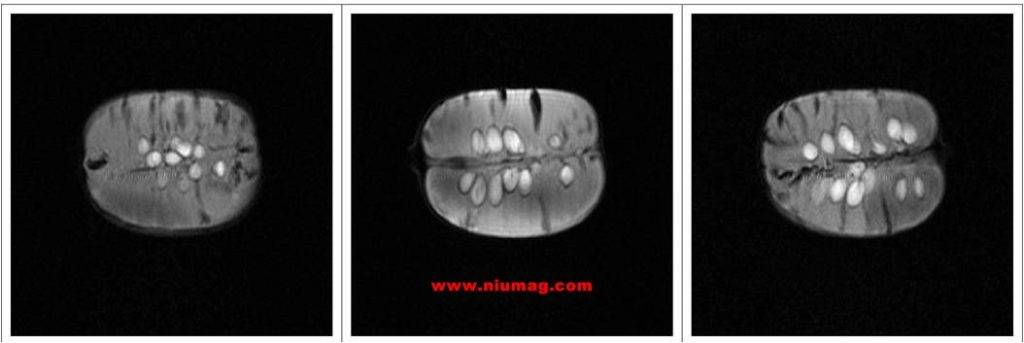

蜜桔核磁共振多層成像圖